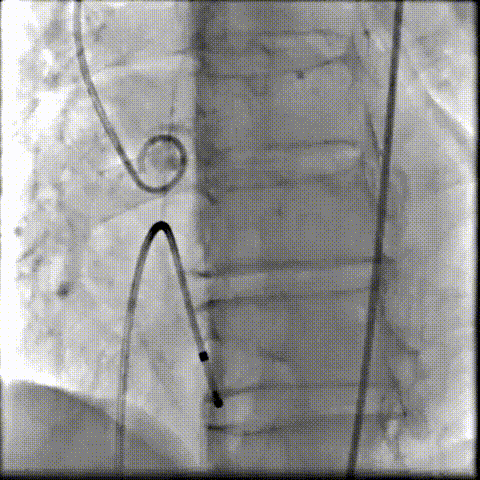

术中影像

根部造影可见返流;20mm球囊预扩,LCA灌注缝隙狭小

预置LCA保护;第一次释放,

团状钙化挤压导致瓣膜(AV23)少量下滑

回收后重新定位,第二次释放,

瓣膜(AV23)深度仍未达到最佳预期

完全回收,第三次定位释放,瓣膜(AV23)位置良好

瓣膜工作位释放“烟囱支架”;

瓣膜(AV23)完全释放后,“烟囱支架”后扩

最终造影,“烟囱支架”显影清晰,瓣膜形态及LCA灌注良好